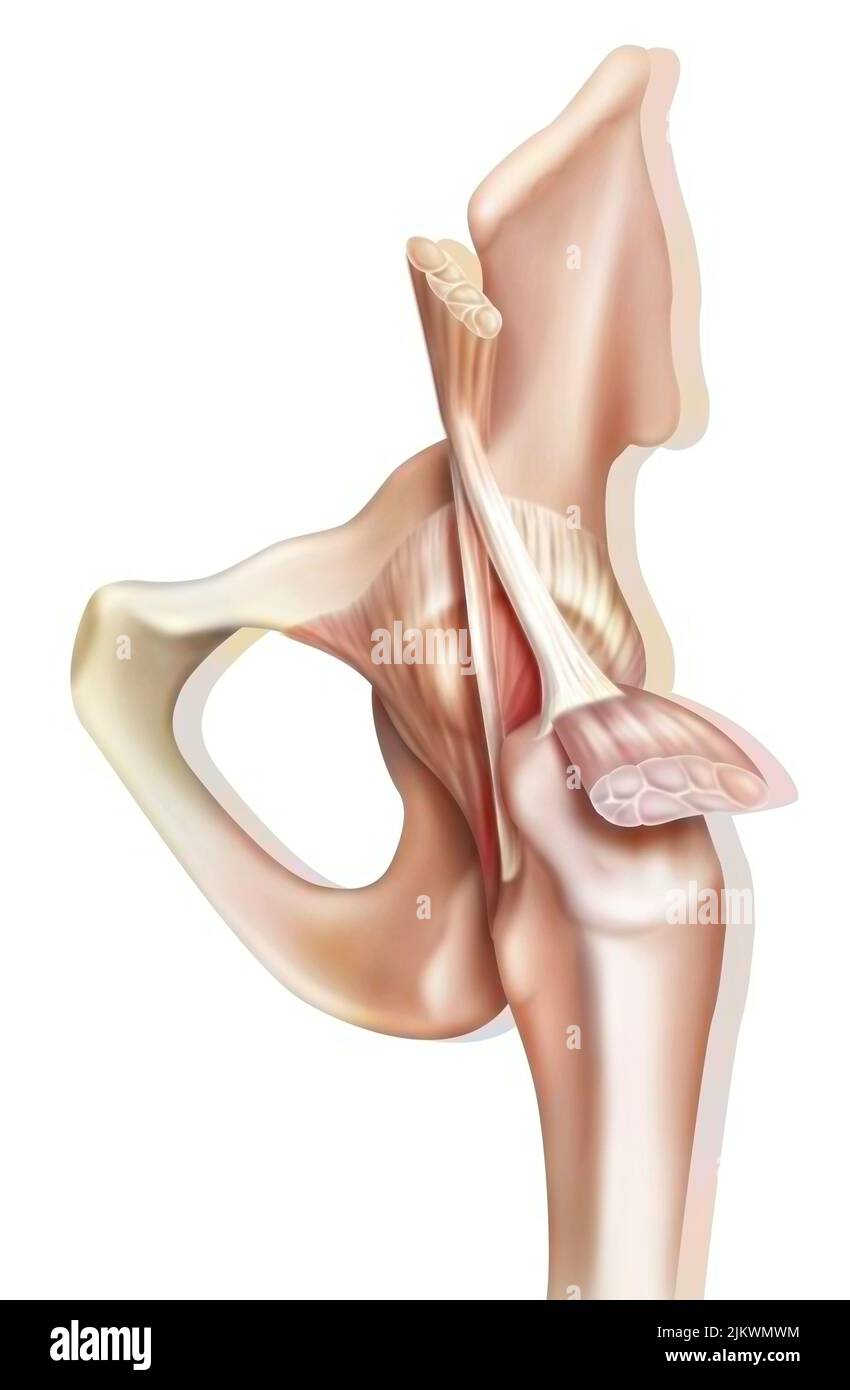

Bone joint of the hip without and with the coxofemoral joint capsule. Stock Photohttps://www.alamy.com/image-license-details/?v=1https://www.alamy.com/bone-joint-of-the-hip-without-and-with-the-coxofemoral-joint-capsule-image476923594.html

Bone joint of the hip without and with the coxofemoral joint capsule. Stock Photohttps://www.alamy.com/image-license-details/?v=1https://www.alamy.com/bone-joint-of-the-hip-without-and-with-the-coxofemoral-joint-capsule-image476923594.htmlRF2JKWMWE–Bone joint of the hip without and with the coxofemoral joint capsule.

Anatomy of the coxofemoral (hip) joint with muscles, tendons. Stock Photohttps://www.alamy.com/image-license-details/?v=1https://www.alamy.com/anatomy-of-the-coxofemoral-hip-joint-with-muscles-tendons-image476923600.html

Anatomy of the coxofemoral (hip) joint with muscles, tendons. Stock Photohttps://www.alamy.com/image-license-details/?v=1https://www.alamy.com/anatomy-of-the-coxofemoral-hip-joint-with-muscles-tendons-image476923600.htmlRF2JKWMWM–Anatomy of the coxofemoral (hip) joint with muscles, tendons.

Anatomy of the coxofemoral (hip) joint with muscles, tendons. Stock Photohttps://www.alamy.com/image-license-details/?v=1https://www.alamy.com/anatomy-of-the-coxofemoral-hip-joint-with-muscles-tendons-image476923664.html

Anatomy of the coxofemoral (hip) joint with muscles, tendons. Stock Photohttps://www.alamy.com/image-license-details/?v=1https://www.alamy.com/anatomy-of-the-coxofemoral-hip-joint-with-muscles-tendons-image476923664.htmlRF2JKWN00–Anatomy of the coxofemoral (hip) joint with muscles, tendons.